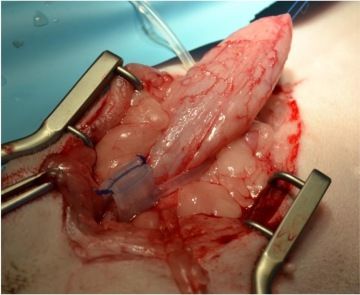

Lumbosakrální spinální stabilizace

Jedny z nejnáročnějších operací jsou zákroky na deformované páteři francouzských buldočků a mopsů. Vyžadují předchozí CT a MRI vyšetření, speciální 3D tištěné vrtací šablony pro bezpečné usazení implantátů a v zásadě vytvoření nové podpůrné páteře z polymetylakrylátu (kostní cement). Takové zákroky trvají i několik hodin a vyžadují extenzivní plánování a maximální soustředění celého operačního týmu během celého zákroku.

Asi si dokážete představit úlevu, když se váš pacient po takovém zákroku postaví a udělá první vrávoravé kroky.

Náročné jsou zákroky na játrech s vrozenými cévními anomáliemi, kde hrozí neustálé riziko těžkého krvácení pacienta. Mám rád operace hrudníku, které jsou zvláštní z pohledu přítomnosti bijícího srdce pacienta.